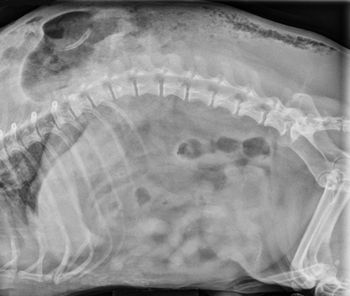

A contrast enema study helped clinicians detect an intestinal stricture in this exotic pet. See how this diagnostic step can help your reptile patients with similar signs.